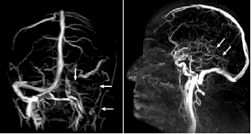

经检查,刘同学的大脑状态在短时间内急剧恶化,多处脑出血和肿胀、头颅CT血管影像中很多静脉血管消失。

图2.左图示左静脉窦及颈静脉均无血流;

右图示深部静脉系统无血流(→)。